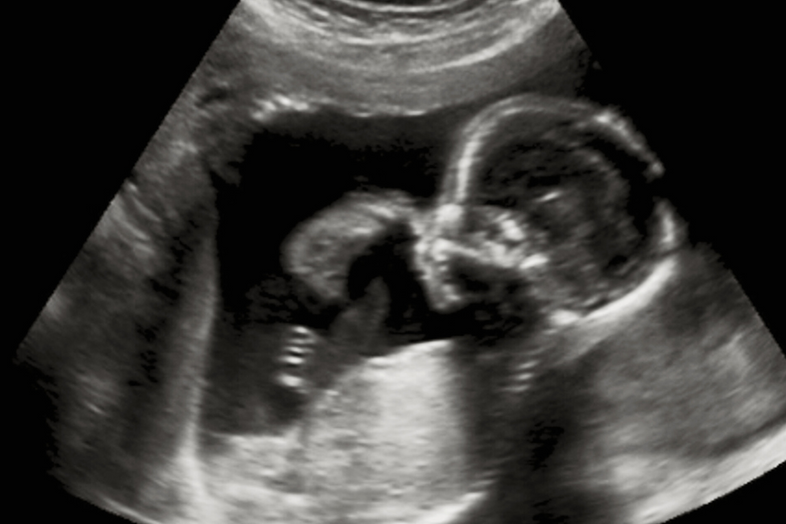

With the combination of these methods and accurately timing my peak fertility using Mira, we were finally able to get pregnant this time. Mira has been instrumental in helping me understand my body's rhythms and aiding us in achieving our dream.